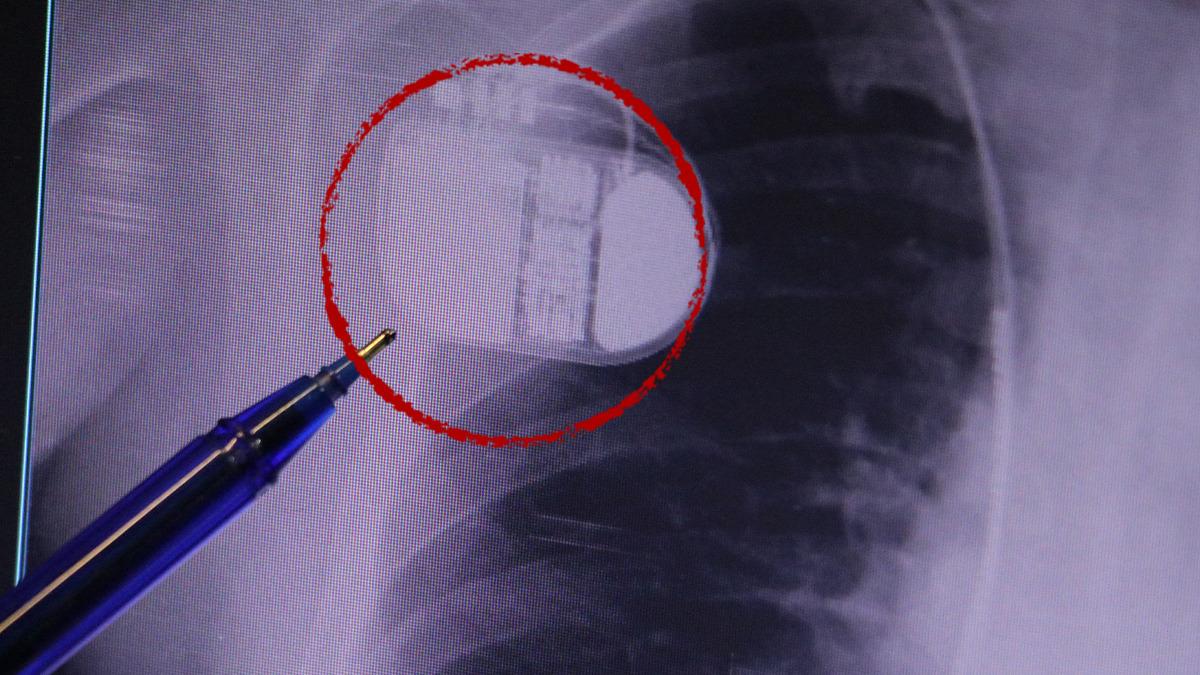

Kalp krizi sonrası kalp dokusunun zarar gördüğünü belirten İsmail Erdoğu, şöyle konuştu: “Kalp hastalığı günümüzde dünyada en sık görülen ölüm nedenlerinden biridir. Kalp hastalıklarının pek çok grubu vardır. Kalp hastalığı dediğimizde sadece kalpte stent bulunan ve damar sorunları olan kişileri kastetmiyoruz. Aynı zamanda hipertansiyon ve şeker hastalığı olan hastalar da kalp hastalığına adaydır. Toplumun yaklaşık %30-35’ini kapsıyoruz. Oldukça yaygın bir hastalıktır ve bu konuda teknolojik ve tıbbi anlamda ciddi gelişmeler yaşanmıştır. Son 30 yılda insanlar kalp rahatsızlığı nedeniyle hastaneye kaldırıldı.” “Hastaneye yattıktan sonra hayatta kalmak artık mümkün. Kalp krizinden kurtulmanın belli bir maliyeti var. Kalp krizinden sonra kalp yetmezliği ortaya çıkıyor. Kalp yetmezliği olan hastalarda aritmiler, ani ölümler gibi sorunlar ortaya çıkabiliyor. Hastaların bu uzun vadeli rahatsızlıklardan kendilerini korumak için mutlaka kalp piline ihtiyaçları var” dedi.

MR makinesine kalp pili takılmasının mümkün olduğunu belirten Erdoğu, şöyle konuştu: “Çok büyük bir ameliyat değil ama yine de ciddi bir cerrahi işlem. Kalp pili tıpta son 30 yılın en büyük gelişmesi. Aslında bilgisayarın minyatürleştirilmiş hali olup insan vücuduna yerleştirilen bir tedavi. İnsan ömrünü önemli ölçüde uzatan bir tedavi. İnsanlar şokla hayata tutunurken, pil olmasaydı öleceğini düşündüğümüz çok sayıda hastamız var. Bu özelliğimiz Kalp pili uygun hastalarda ani ölümü önler, ritmi düzeltecek sağlık uzmanı ya da defibrilatör yoksa hastayı hayatta tutmak mümkün değildir. Hastalarımız “kalp pilim var” dediğinde hastalıktan kurtulurlar. Örneğin mikser kullanmak ya da kolu sallayacak herhangi bir hareket kalp pilini olumsuz etkileyebilir. Soğuk havalarda vücutta meydana gelen şiddetli titremeler kalp pilinin hafızasını karıştırıp gereksiz şoklara neden olabilir.